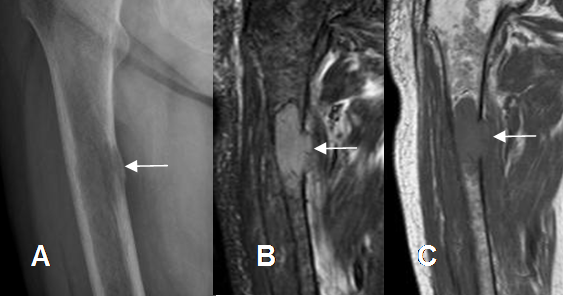

Fig 191. Plasmocitoma solitario.

A: Rx AP, B: RM coronal en STIR y C: RM coronal en T1. Lesión lítica en la diáfisis femoral, con ruptura de la cortical, por plasmocitoma solitario.